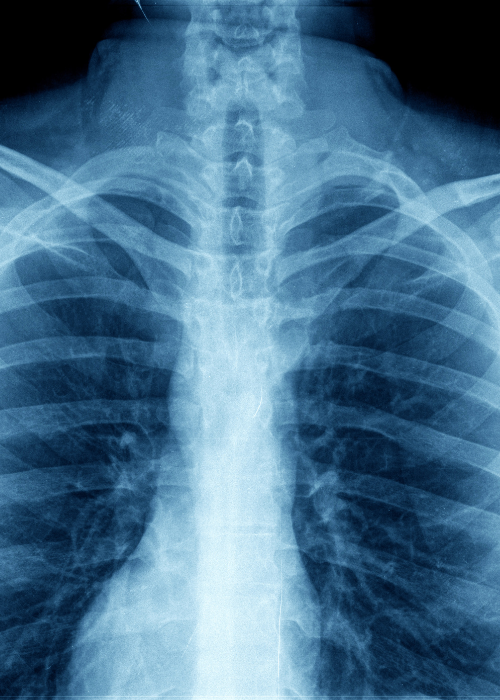

We provide expert assessments and reports to support claims against the Road Accident Fund, ensuring victims receive fair compensation for injuries sustained in vehicular accidents.

Birrell and Associates specialises in medico-legal services, specifically Road Accident Fund claims. We connect clients with top medical experts to provide comprehensive evaluations and expert testimony tailored to each case.

In such cases, especially concerning Orthopaedic reports required for legal proceedings, we arrange for the client to be re-examined by another partner or associate for a nominal fee. This ensures the continuity and reliability of the report and any necessary re-examinations.